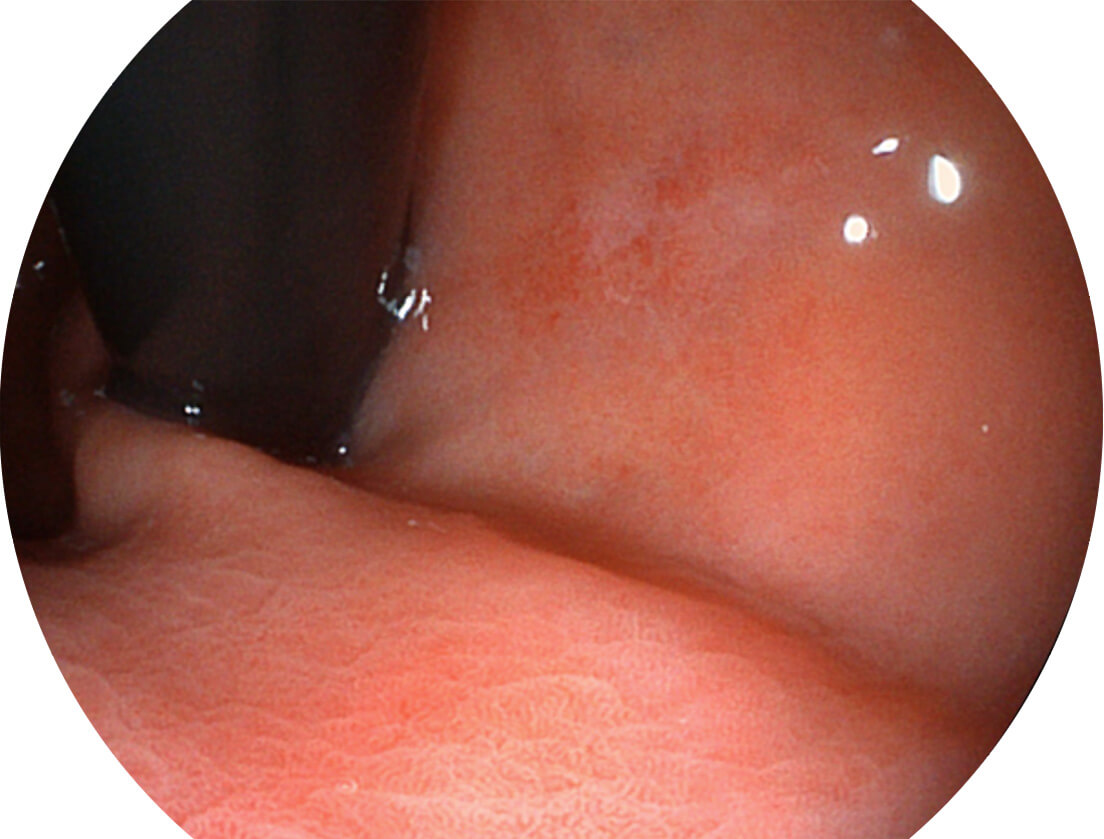

采用光路合束技术,光谱自由度高,实现了更丰富的照明模式,染色模式SFI及VIST,从远景到近景,助力消化道早期疾病诊断。

送水方向与手术器械方向,两者更贴合,能快速冲洗黏膜表面的粘液及出血,发现病变和出血点。